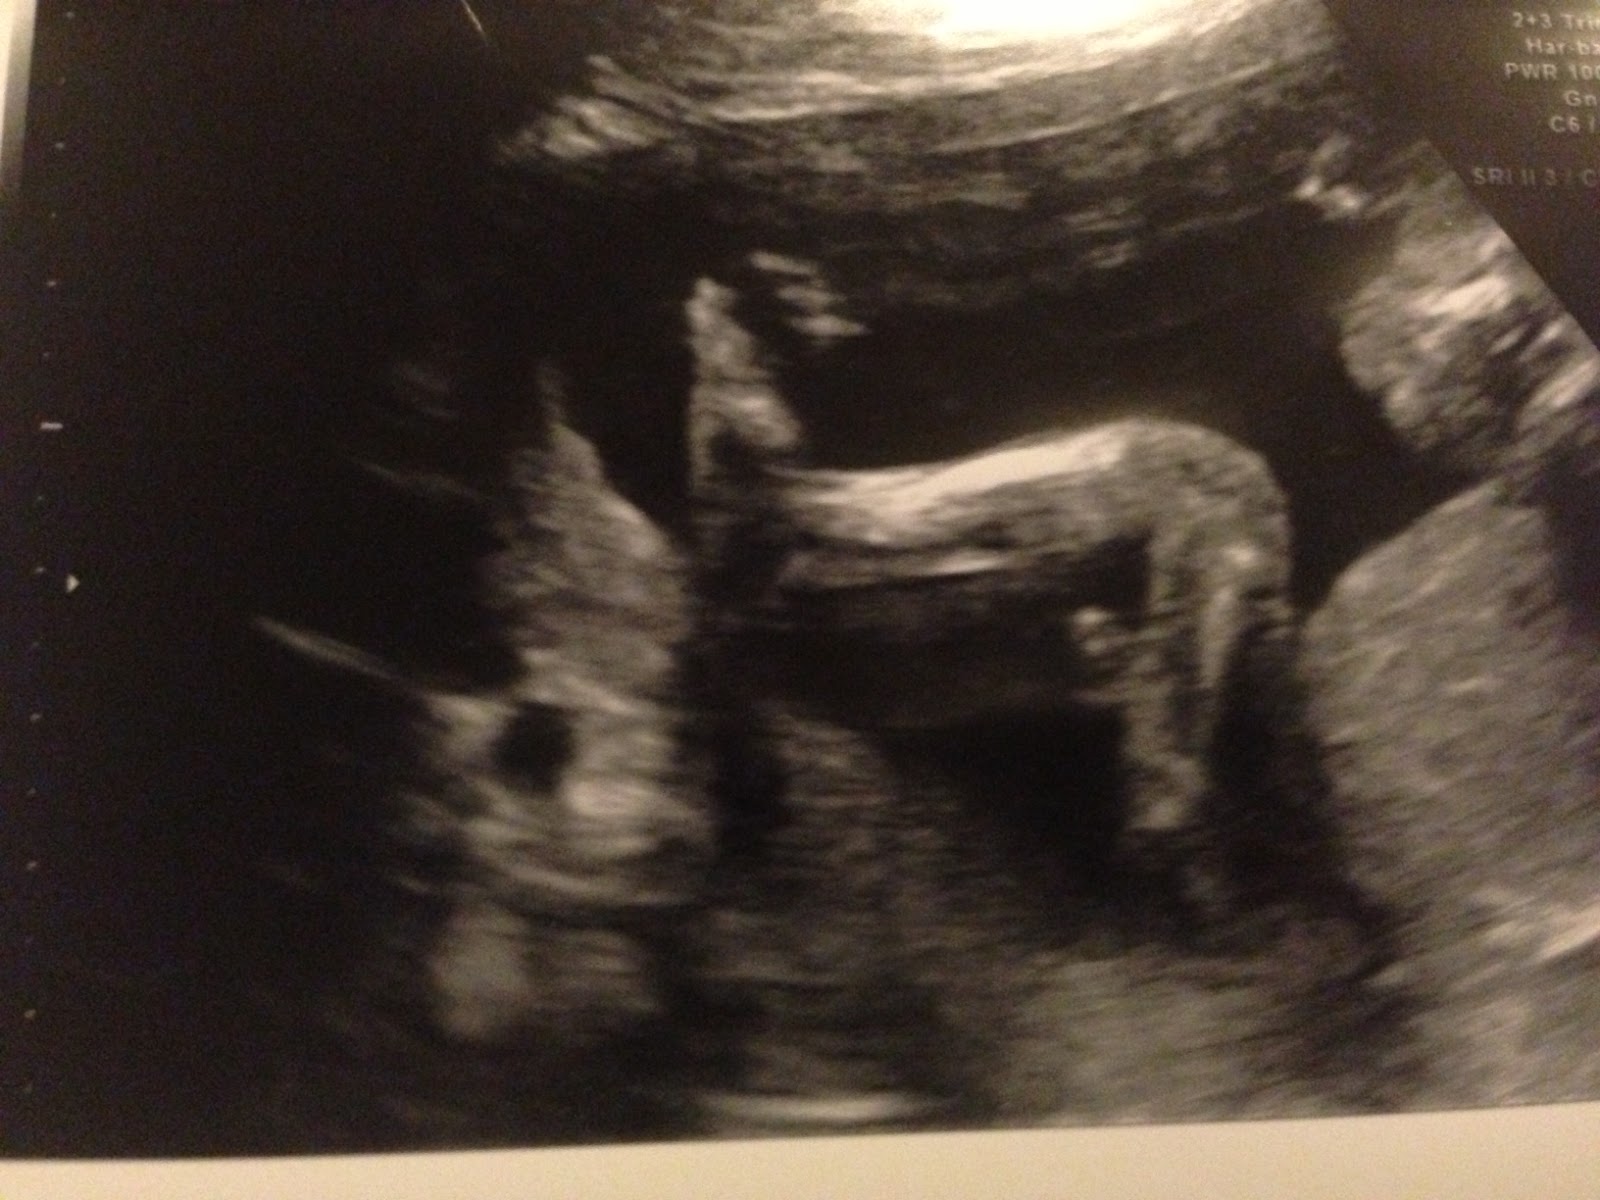

(por isso, hoje só tem som e imagens!)

Rostinho com a mãozinha na boca

Pernoca

159bpm

Cecília !!!!!!